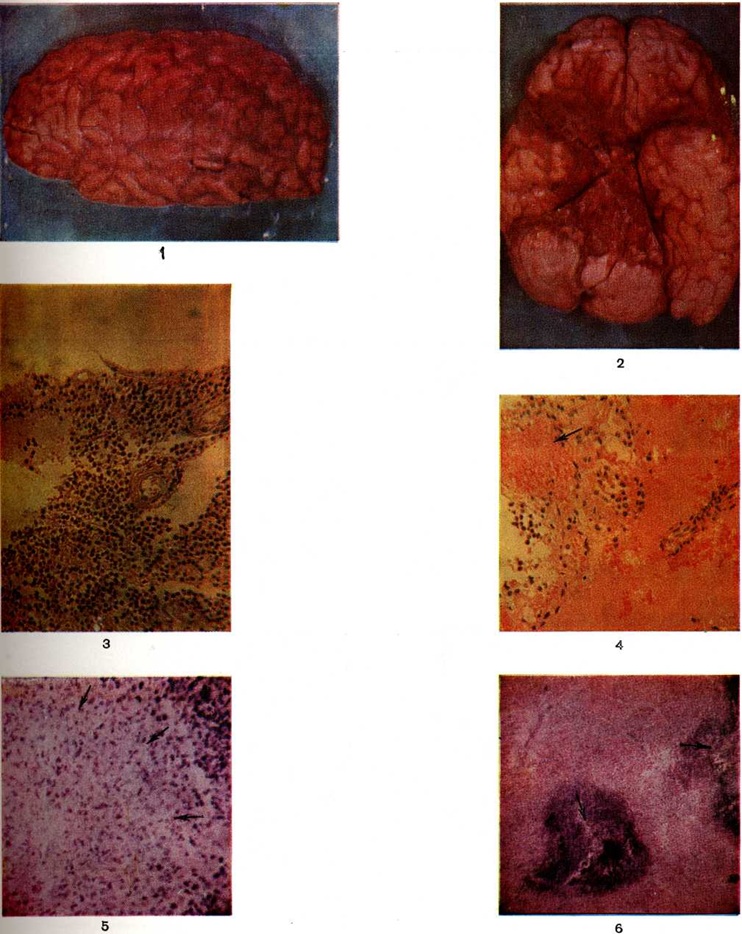

Большинство нем. клиницистов высказывались против разграничения этих понятий, считая, что токсическое раздражение мозговых оболочек вначале вызывает явления менингизма, а при более резком раздражении — серозное воспаление. Ф. Видаль (1910), Неттер (Е. Netter, 1912) и другие признавали возможность дальнейшего перехода серозного Менингит в гнойный асептический в связи с проникновением в жидкость лейкоцитов из гиперемированных оболочек. В начале 20 век взгляд на серозный Менингит изменился. Л. О. Даркшевич (1909) выделил в серозном Менингит первичный, являющийся самостоятельным инфекционные заболеванием, и вторичный, который может возникнуть при любой инфекции, интоксикации или травме. Валльгрен (A. J. Wallgren) в работе «Новое инфекционное заболевание центральной нервной системы» описал в 1925 год эпидемический вспышку острого серозного Менингит, названного им «асептический серозный менингит». Армстронг и Лилли (Ch. J. Armstrong, R. D. Lillie, 1934) выделили особый вирус, являющийся возбудителем одной из форм серозного Менингит — хориоменингита. Позднее была доказана роль энтеровирусов Коксаки и ECHO в этиологии серозного Менингит, а также существование серозного Менингит, вызываемого вирусом полиомиелита. КлассификацияСуществует несколько классификаций Менингит По характеру воспалительного процесса в оболочках и изменений цереброспинальной жидкости различают серозный и гнойный Менингит Первичный Менингит развивается без предшествующей общей инфекции или заболевания какого-либо органа, вторичный — является осложнением других инфекционные заболеваний, воспалительных и невоспалительных поражений органов и систем. Вторичный Менингит, возникающий при опухолях мозга, коллагенозах, всегда протекает как серозный. По этиологии различают: I. Бактериальный менингит. А. Гнойные формы: а) менингококковый (эпидемический цереброспинальный); б) пневмококковый; в) вызванный палочкой Афанасьева—Пфейффера; г) стрептококковый; д) стафилококкоковый; е) гонококковый; ж) вызванный синегнойной палочкой; з) сальмонеллёзный; и) брюшнотифозный (паратифозный); к) колибациллярный; л) листериозный. Б. Серозные формы: а) туберкулёзный; б) сифилитический; в) микоплазменный; г) лептоспирозный. II. Вирусный менингит (серозный): а) острый доброкачественный лимфоцитарный хориоменингит; б) вызванный вирусом эпидемического паротита; в) вызванный энтеровирусами (ECHO и Коксаки); г) герпетический; д) гриппозный. Менингит, вызванный грибками и простейшими (серозный или гнойный): а) бластомикозный; б) кокцидиоидозный; в) токсоплазменный; г) кандидозный; д) мукорозный; е) амёбный. В зависимости от развития и течения выделяют молниеносный, острый, подострый и хронический Менингит По преимущественной локализации воспалительного процесса Менингит бывает базальным, конвекситальным, мезодиэнцефальным, спинальным. Этиология и эпидемиологияГнойный Менингит описан почти при всех бактериальных инфекциях и при инфекциях, вызванных простейшими и грибками, но в большинстве случаев он вызывается сравнительно небольшой группой микробов: менингококками (30—74%), пневмококками (14—55%) и гемофильной палочкой инфлюэнцы Афанасьева—Пфейффера (8—13%). Участились случаи стафилококкового Менингит и Менингит, вызванного синегнойной палочкой. По данным Смита (Н. V. Smith, 1954), на Американском континенте палочка инфлюэнцы является самым частым возбудителем гнойного Менингит у детей, что связывают с широким применением антибиотиков, действующих преимущественно на кокки. По данным С. Л. Кипнис (1971), среди гнойных Менингит менингококковый Менингит встречается в 59,4%, пневмококковый — в 16,4% , Менингит, вызванный палочкой инфлюэнцы—в 5,9% , стафилококковый—в 2,5%, Менингит, вызванный Esherichia coli — в 2,3% , стрептококковый — в 0,4%, грибковый — в 0,5% , паратифозный — в 0,1% случаев; в 12,5% случаев этиология гнойного Менингит не выяснена. Отмечающийся рост числа случаев гнойного Менингит с невыясненной этиологией, по-видимому, связан с широким применением антибиотиков в амбулаторных условиях. Наблюдаются эпидемические вспышки серозного Менингит энтеровирусной этиологии. Энтеровирусная инфекция получила распространение практически во всех частях земного шара. Первые сведения об эпидемиях энтеровирусного Менингит, имеющие вирусологический подтверждение, получены в 1954 году США. В Европе (Швеция) с 1954 год официально зарегистрировано учащение случаев эпидемического серозного Менингит Особенно большое распространение энтеровирусная инфекция получила в летне-осенние месяцы в 50-е годы в Англии, Бельгии, Нидерландах, Швеции, Норвегии, Америке. Так, вспышка серозного Менингит в Бельгии в 1956 год охватила 10% населения страны. В США в 1957 год в штате Миннесота заболело около 400 000 человек, в Милуоке — около 280 000 человек, то есть 4% населения. ПатогенезВысокая частота Менингит в детском возрасте обусловлена недостаточностью иммунитета к инфекциям и несовершенством гематоэнцефалического барьера. У грудных детей возможен также непосредственный доступ возбудителя к мозговым оболочкам через отверстия решетчатой кости, в которых проходят отростки мягкой мозговой оболочки. Входными воротами инфекции при Менингит являются слизистая оболочка носоглотки, бронхов, желудочно-кишечные тракта. Возможна передача инфекции внутриутробно через плаценту. Возбудитель, попав на слизистую оболочку, вызывает местные воспалительные изменения различной степени выраженности: назофарингит, ангину, бронхит, желудочно-кишечные расстройства. Распространяясь лимфогенным или гематогенным путём, инфекция попадает далее в мозговые оболочки. Циркуляция возбудителя в крови клинически может проявляться симптомами общей интоксикации. Иногда этот период бывает настолько коротким, что совпадает по времени с появлением признаков поражения мозговых оболочек. Распространение возбудителей Менингит в организме может происходить также из любого воспалительного очага [пневмония, фурункул, рожа, кишечная инфекция, инфекции желчного и мочевого пузыря, воспаление придаточных пазух носа (околоносовых, Т.), среднего уха, глазного яблока, орбиты и так далее]. В этом случае речь идёт о развитии вторичного метастатического гнойного Менингит Наряду с гематогенно-генерализованным возможен и сегментарно-васкулярный путь распространения возбудителя. В этих случаях инфекция распространяется по регионарным сосудам, имеющим связь с мозговыми сосудами, минуя общее кровяное русло. Нередким является контактный путь перехода инфекции на оболочки, например, при гнойных отитах, мастоидитах, эпитимпанитах, церебральных абсцессах, тромбофлебите вен и синусов твёрдой мозговой оболочки. Менингит может также развиваться при открытой черепно-мозговой и позвоночно-спинальной травме, при переломах и трещинах основания черепа, сопровождающихся ликвореей. Травматический Менингит бывает, как правило, гнойным. Патологическая анатомияПатологоанатомические изменения при лептоменингите наблюдаются не только в мягких мозговых оболочках головного и спинного мозга, но также в эпендиме и сосудистых сплетениях желудочков. Форма воспаления мягких оболочек, как правило, обусловлена свойствами возбудителя. Так, серозный Менингит чаще вызывается вирусами, гнойный — бактериальной, в основном кокковой, флорой, а хронический продуктивное воспаление — грибками и простейшими (токсоплазмоз). Однако эта закономерность имеет относительное значение, потому что при гнойном Менингит в первые двое суток экссудат серозный, а при вялом течении гнойного или серозно-фибринозного процесса воспаление приобретает свойства хронического продуктивного. Воспалительный выпот в мягких оболочках всегда заметнее на основании головного мозга, где он скапливается в зоне перекрёста зрительных нервов, на нижнебоковой поверхности моста (варолиева моста), мозжечка и продолговатого мозга, то есть в области расположения наиболее крупных субарахноидальных ликвороносных вместилищ — цистерн. Полости или более обширные скопления экссудата можно наблюдать также на территории лобно-теменно-височных долей полушарий по ходу латеральной (сильвиевой) и других глубоких борозд, где он окутывает проходящие здесь субарахноидально сосуды, расслаивая листки мягкой мозговой оболочки. Экссудат можно видеть и в спинальных оболочках, где воспалительные изменения обычно появляются на 1—2 дня позже. Чаще поражаются покровы задней поверхности спинного мозга в области шейного и поясничного утолщений. При остром серозном лептоменингите серовато-желтоватый желатинозный экссудат скапливается в подпаутинном пространстве головного (цветной рисунок 1) и спинного мозга, обволакивая проходящие здесь крупные сосуды и нервные стволы, заполняет желудочки мозга. Мягкие оболочки, эпендима и сосудистые сплетения при этом гиперемированы, отёчны, тускловаты, с единичными или множественными кровоизлияниями. Гистологически обнаруживают картину острого серозного или серозно-фибринозного лептоменингита, эпендиматита и хориоидита (смотри полный свод знаний Хориоэпендиматит). В инфильтрате преобладают лимфоциты, макрофаги и плазмоциты (рисунок 1; и цветной рисунок 3 и 4). Воспаление носит очаговый или диффузный характер с выраженным перифокальным отёком. В связи с гиперпродукцией цереброспинальной жидкости может возникнуть острая гидроцефалия (смотри полный свод знаний), отёк и набухание головного мозга (смотри полный свод знаний) с вклинением его вещества в большое затылочное отверстие. Как правило, воспалительный выпот подвергается резорбции с полной ликвидацией патологический процесса. Однако иногда экссудат организуется, что сопровождается образованием между листками лептоменингоспаек, рассекающих подпаутинное пространство на отдельные замкнутые, переполненные цереброспинальной жидкостью полости — кисты. Микроскопически при этом обнаруживается пролиферация менинготелия и эпендимарных клеток и очаговая инфильтрация оболочек и сплетений лимфоцитами, макрофагами и плазмоцитами, а также новообразование соединительной ткани. Такая форма заболевания носит название хронический серозного или кистозного лептоменингита.

При гнойном Менингит воспалительный выпот имеет сначала серозный характер, а на 2—3-й день заболевания он приобретает вид гнойного экссудата. При этом мягкие оболочки полушарий мозга (цветной рисунок 1), сосудистые сплетения и эпендима пропитаны мутной желтовато-зеленоватой вязкой ЖИДКОСТЬЮ. При обильном накоплении гнойнофибринозный экссудат образует «чепчик» в лобной и теменной долях полушарий (цветной таблица, ст. 33, рисунок 2) или окутывает весь мозг сплошной массой. Он заполняет также мозговые полости, покрывая желтоватой плёнкой сплетения и стенки желудочков. Развивающаяся обтурация ликворных путей выпотом ведёт к острому расширению желудочков мозга (цветной рисунок 3) и церебральной гипертензии. В воспалительный процесс могут вовлекаться подоболочечные отделы мозгового вещества, но особенно часто области, окружающие желудочки. При своевременно начатом лечении гнойный экссудат подвергается ферментативному распаду и резорбции, но в некоторых случаях он организуется, вызывая спаечный процесс в оболочках и желудочках мозга. Развивается хронический гнойный или хронический продуктивный (адгезивный) лептоменингит, характеризующийся частичной облитерацией подпаутинного пространства с образованием между листками мягкой оболочки замкнутых гнойных или серозных полостей. Спайки могут рассекать также и желудочки мозга, формируя отдельные заполненные гноем или цереброспинальной жидкостью камеры. Макроскопическую картину хронический продуктивного Менингит дополняет склероз оболочек, сплетений и эпендимы с полной или частичной облитерацией находящихся здесь сосудов. Резко нарушаются циркуляция цереброспинальной жидкости и мозговая гемодинамика, что ведёт к развитию гидроцефалии. Гистологически в оболочках, эпендиме и сплетениях обнаруживается картина хронический гнойного воспаления с выраженными склеротическими изменениями. В соседних участках мозговой ткани можно наблюдать поля клеточного опустошения с дистрофией и гибелью нейронов и накоплением в них липофусцина, демиелинизацию нервных волокон и очаговый глиоз. Описанные изменения могут выявляться и без предшествующей клиники острого Менингит, через несколько лет после травмы, инфекционного заболевания или оперативного вмешательства. Если в оболочечном выпоте содержатся эритроциты и, следовательно, мягкие мозговые оболочки окрашиваются в различные оттенки красного цвета, то такое воспаление этих оболочек носит название геморрагического (цветной рисунок 2). Геморрагический лептоменингит (цветной рисунок 4) может осложнить инфекционные заболевание, сопровождающееся общим тромбогеморрагическим синдромом или местной гиперергической реакцией немедленного типа. Сходную макроскопическую картину из-за примеси крови имеет реактивное воспаление в зоне субарахноидального кровоизлияния. Дифференциальной диагностике в этих случаях может помочь гистологический исследование материала — при инфекционном геморрагическом Менингит обнаруживают фибриноидные некрозы сосудов (смотри полный свод знаний Фибриноидное превращение), их тромбоз и преимущественно гранулоцитарную инфильтрацию очага воспаления. Туберкулёзный лептоменингит — результат гематогенной генерализации или лимфогенного распространения инфекции из лёгочного, лимфожелезистого (или другого внелёгочного) очага. Современные методы лечения изменили морфологический картину заболевания. На смену острому серозно-фибринозному воспалению оболочек мозга, дававшему раньше почти 100% летальность, пришли хронический ограниченные формы поражения со значительно лучшим прогнозом. При остром туберкулёзном Менингит желатинозный серовато-желтоватый выпот обнаруживается в подпаутинном пространстве головного (цветной рисунок 5) и спинного мозга в типичных местах, а также в полостях мозга. В мягкой оболочке и в эпендиме заметны милиарные или более крупные сероватые бугорки (цветной рисунок 6). Пропитанная серозно-фибринозным выпотом ткань может подвергаться казеозному некрозу (цветной рисунок 7). Микроскопически в инфильтрате с первых же дней заболевания преобладают лимфоциты. Самой характерной гистологический чертой подострых и хронический форм туберкулёзного воспаления является образование преимущественно эпителиоидно-клеточных гранулем (цветной рисунок 5), нередко с казеозным некрозом их центра. Подобные гранулемы обнаруживаются и в стенке сосудов, в которых можно видеть также и другие изменения — от серозного пропитывания до фибриноидного и казеозного некроза с тромбозом и развитием инфарктов головного мозга. При туберкулёзном Менингит в воспалительный процесс часто вовлекаются смежные отделы мозговой ткани, в которой развивается картина казеозного (цветной рисунок 6) или гранулематозного (рисунок 2) энцефалита. В исходе туберкулёзного воспаления в субарахноидальном (и даже субдуральной) пространстве головного и спинного мозга могут возникать спайки. Просвет проходящих здесь сосудов облитерируется (рисунок 3 и 4), что приводит к тяжёлым нарушениям циркуляции цереброспинальной жидкости и к расстройству гемодинамики. При амёбном Менингит (менингоэнцефалите), вызываемом неглериями, патолого-анатомически выявляется гнойный лептоменингит, геморрагический некротизирующий менингоэнцефалит, отёк мозга, периваскулярные скопления амёб. Морфологически картина при менингоэнцефалите акантамебного происхождения проявляется гранулематозным энцефалитом с очаговыми некрозами. Клиническая картинаМенингеальный синдром и изменения цереброспинальной жидкостиДля всех форм Менингит характерно наличие симптомов, объединяемых в менингеальный, или оболочечный, синдром. Полный менингеальный симптомокомплекс наблюдается не всегда даже при гнойном Менингит Нередко, особенно у детей раннего возраста, лиц старческого возраста, выявляется лишь часть менингеальных симптомов. К менингеальному синдрому относятся головная боль, рвота, общая гиперестезия, специфическая менингеальная поза, ригидность затылочных мышц, симптомы Кернига, Брудзинского, симптом подвешивания Лесажа, скуловой симптом Бехтерева н другие Головная боль — постоянный симптом, наблюдается практически у всех больных при различных формах Менингит Она может быть диффузной или локализованной (преимущественно в области лба и затылка). Возникновение головной боли связано с раздражением чувствительных окончаний тройничного нерва, а также парасимпатических (блуждающий нерв) и симпатических волокон, иннервирующих оболочки головного мозга. Рвота обычно сопровождает головную боль, возникает без связи с приёмом пищи, имеет «фонтановидный» характер. Рвота при Менингит— центрального происхождения и связана с раздражением рецепторов блуждающего нерва пли его ядер, расположенных на дне IV желудочка, или рвотного центра в ретикулярной формации продолговатого мозга. Важным симптомом является общая кожная гиперестезия и повышенная чувствительность к звуковым и световым раздражителям (гиперакузия, светобоязнь). Выявление этого симптома в раннем детском возрасте затруднено, так как дети обычно негативно относятся к осмотру, раздражаются при прикосновении к ним, капризничают, отворачиваются при ярком свете. В основе общей гиперестезии лежит раздражение задних корешков, а возможно и клеток спинномозговых узлов. Характерна поза больного: запрокинутая голова, выгнутое туловище, «ладьевидный» втянутый живот, руки прижаты к груди, ноги подтянуты к животу (менингеальная поза, поза «лягавой собаки», «взведённого курка»). Менингеальная поза — следствие рефлекторного тонического сокращения мышц. Запрокинутая голова больного обусловлена ригидностью затылочных мышц — повышением тонуса мышц-разгибателей шеи. При попытке наклонить вперёд голову больного, находящегося в положении лёжа, выявляется напряжение мышц затылка, при этом подбородок больного привести к грудной клетке не удаётся. Любая попытка вывести голову больного из её фиксированного положения сопровождается резкой болезненностью. Симптом Кернига (смотри полный свод знаний Кернига симптом) — очень ранний и характерный симптом поражения мозговых оболочек. Он выражается в невозможности разогнуть в коленном суставе ногу, предварительно согнутую под прямым углом в коленном и тазобедренном суставах (рисунок 5). Следует отличать симптом Кернига от анталгического (мышечного) сопротивления при симптоме Ласега (смотри полный свод знаний Радикулит). У детей раннего возраста симптом Кернига может не выявляться. У новорожденных и детей первых двух месяцев жизни, а также у больных паркинсонизмом, миотонией симптом Кернига может быть следствием физиологический или патологический повышения общего тонуса мышц. Верхний симптом Брудзинского выражается в непроизвольном сгибании ног в коленных суставах в ответ на попытку привести голову к груди в положении лёжа на спине (рисунок 6). Скуловой симптом Брудзинского — та же реакция при перкуссии скуловой дуги. Лобковый симптом Брудзинского выражается в сгибании ног в коленных суставах при надавливании на лонное сочленение. Нижний симптом Брудзинского исследуется одновременно с симптомом Кернига: при попытке разогнуть ногу в коленном суставе вторая нога сгибается в колене и приводится к животу. Симптом Гийена аналогичен нижнему симптому Брудзинского — при сдавливании четырех-главой мышцы одной ноги другая нога сгибается в колене и приводится к животу. Напряжение длинных мышц спины является также частым и типичным признаком менингеального синдрома и выявляется в виде следующих симптомов. Симптом Мейтуса: больному, лежащему на спине, фиксируют разогнутые в коленях ноги правой рукой, а левой рукой поддерживают спину, помогая ему сесть. При менингеальном синдроме спина больного и разогнутые ноги в положении сидя образуют тупой угол: больной не может сидеть прямо при разогнутых ногах. Симптом Фанкони — невозможность самостоятельно сесть в постели при разогнутых и фиксированных коленях. Симптом «треножника» — больной может сидеть в кровати, лишь опираясь руками позади спины. Симптом «поцелуя колена» — больной не в состоянии даже при согнутых в тазобедренных суставах нижних конечностях прикоснуться губами к колену. Довольно постоянным у больных всех возрастов является скуловой симптом Бехтерева: при перкуссии скуловой дуги усиливается головная боль и непроизвольно возникает болезненная гримаса на соответствующей половине лица. У детей раннего возраста определяется симптом подвешивания Лeсажа: поднятый под мышки ребёнок подтягивает ноги к животу и сохраняет их в этом положении, при этом голова слегка запрокинута назад (здоровый ребёнок при этой пробе свободно сгибает и разгибает ноги). Большое диагностическое значение у детей раннего возраста имеет симптом Флатау — расширение зрачков при быстром наклоне головы вперёд.